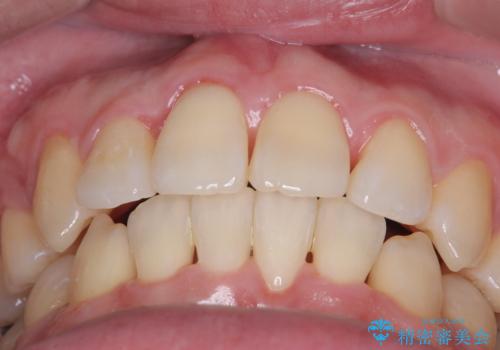

正面から見たときに右上2が全く見えないくらい、右上2が後ろに引っ込んでいる状態でしたが綺麗に並べる事が出来ました。

笑った時のスマイルラインもかなり綺麗になり大変ご満足いただく事が出来ました。

顔貌に対して歯の正中も合いました。